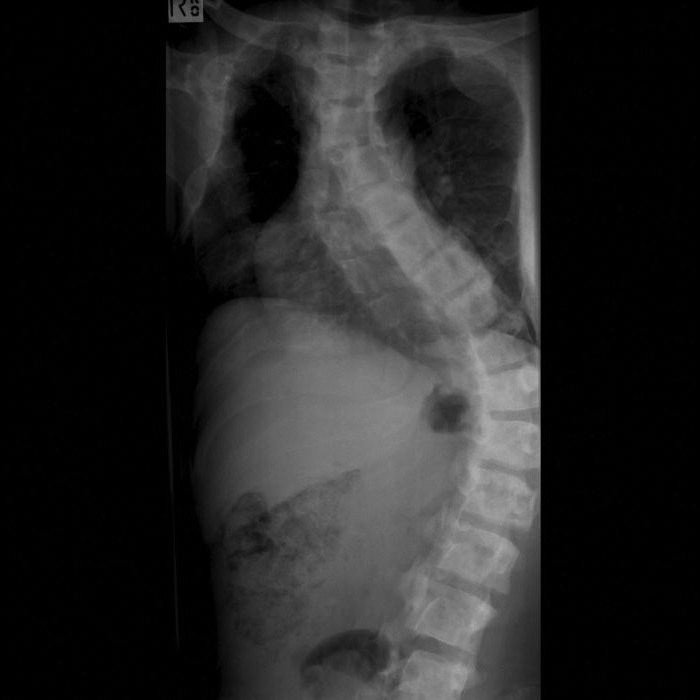

Оце суета. Перше — лікарі намагаються зрозуміти: чи мутує ген GNAS? Для цього існують усілякі аналізи, рентгени, сканування. Справжнє мистецтво розуміння.

- Рентген — наче фото у внутрішній кухні вашого тіла.

Костний спектакль

- Диспропорції в розвитку кісток — кожному своє.

- Переломи на рівному місці — нічого нового, але добряче нагадує про себе.